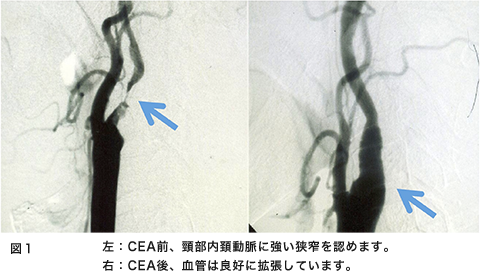

脳の血管が急につまって倒れてしまう病気が脳梗塞です。脳梗塞は様々な原因があるのですが、その一つとして頚部内頚動脈狭窄があります。これは糖尿病、高血圧症、喫煙、高脂血症といった生活習慣病が動脈硬化を来たし、頚部の内頚動脈が細くなり、ここに血栓(小さな血のかたまり)が形成され血液の流れに乗って脳まで流れて脳の血管を詰まらせる、または血管が細くなることで脳の血の巡りが悪くなり脳梗塞を発症します(図1左、図2)。

検査は頚動脈エコー、頸部血管MRA、または血管撮影などがあります。この検査の選択は各施設によって異なります。これらの検査で強い動脈狭窄が発見されたら患者さんと相談して手術治療を考えていくことになります。この手術を頚動脈内膜血栓摘出術(CEA)といいます。簡単に説明すると、動脈硬化で細くなった血管を広げて、脳梗塞の原因となる血の塊(血栓)を取り去ってしまう手術です(図1、図3)。現在最も安全性と治療効果に優れている方法です。この手術の適応で興味のあるところは施設の手術成績によって適応が決定されることです。症状が出現した内頚動脈狭窄症に対してはCEAの合併症が6%以下の施設での手術が有効性であるとされています。別の言い方をするとCEAの合併症が6%以上の施設、術者はこの手術をやってはいけないことになります。